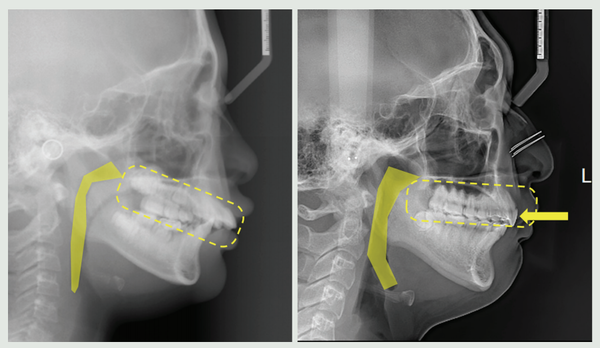

가톨릭대학교 서울성모병원 치과병원 국윤아 교수(교신저자)와 주홍국 원장(맨해 튼치과, 제1저자) 연구팀이 부정교합 환자를 대상으로 치아를 발치하지 않고 후방 이 동하는 교정법을 적용해 3년간 장기 관찰한 결과 치열을 후방이동시켜도 기도공간 에는 문제가 없음을 최초로 규명해 MCPP(Modified C-palatal plate)를 이용한 비발치 교정법의 안정성을 다시금 입증했다.

국윤아 교수 연구팀은 서울성모병원 치과병원에서 2009년부터 2013년까지 상악 치열을 후방 이동하는 치료를 받은 2급 부정교합 청소년 환자 20명(평균 나이 12.9 세)을 대상으로 치료 종료 후 3년의 유지기간 동안 상악결절(위턱 사랑니 뿌리 옆 솟은 부위) 및 기도공간의 부피 변화에 대해 조사했다. 대조군은 교정치료를 받지 않은 청소년 환자 20명(평균 나이 19.3세)으로 선정했다.

연구팀은 치료 전 MCPP 치료 직후 3년 후의 고화질 치과용 CT(CBCT-cone- beam computed tomography) 영상 이미지를 비교해 상악결절 부피 및 기도공간 부피 변화를 측정했다. 그 결과 해당 환자들은 치료 전에 그리고 MCPP를 이용한 상악치열의 후방이동 치료 후 3년 이상의 유지기간 시의 CBCT를 촬영했고 해당 CBCT를 통해 상악결절의 부피와 기도공간의 부피 변화를 측정했다.

MCPP 치료군은 기도공간에 있어 치료 후 유지기간 동안 유의할만한 변화량을 보이지 않았으며 대조군과도 차이가 없었다.

연구결과는 2급 부정교합을 가진 청소년 환자에서 MCPP 교정치료가 기도공간 및 골격적으로 부정적인 영향을 미치지 않는 효과적인 치료방법임을 시사했다. 특히 교 정치료로 인해 치열이 뒤로 밀리면 기도가 좁아지지 않을까 우려하기 쉬운데 골격적 이상이 없다는 점이 입증돼 기도 공간이 좁아질 때 생길 수 있는 수면무호흡증과도 무관하다는 점이 주목할 만하다.

과거 헤드기어와 같이 구외(口外) 장치를 착용해 치료하던 것과 달리 특수하게 고 안된 골격성 고정장치를 입천장에 고정해 심미적으로 효과가 있고 불편감을 최소화하며 어금니와 전체 치열을 치아 뒤쪽 방향으로 이동시키게 된다.